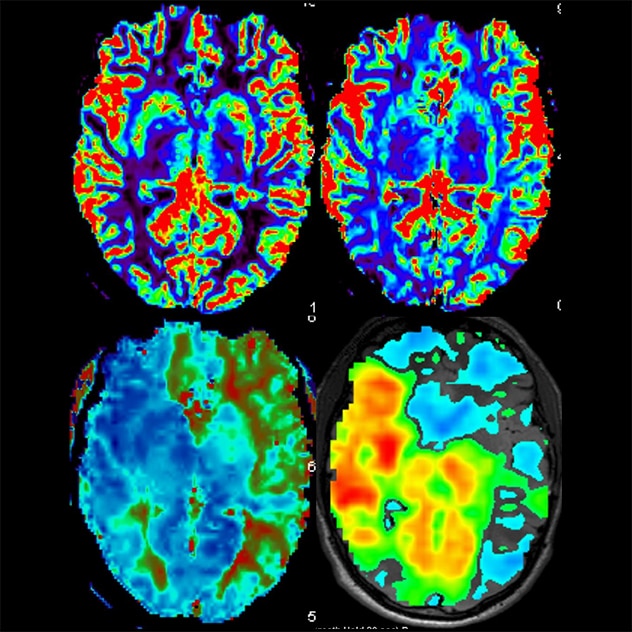

MRI perfusion imaging MRI perfusion imaging

MR perfusion and breath-hold images of a patient with moyamoya disease reveal preserved relative blood flow (top left), mildly elevated relative blood volume (top right), increased thrombotic thrombocytopenic purpura (bottom left) and reduced cerebrovascular reserve (bottom right), predominantly along the left middle cerebral artery and bilateral anterior cerebral artery distributions.